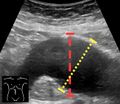

Aortic measurement on abdominal ultrasonography in the axial plane between the outer margins of the aortic wall[37]

Ultrasonography in the sagittal plane, showing axial plane measure (dashed red line), as well as maximal diameter (dotted yellow line), which is preferred